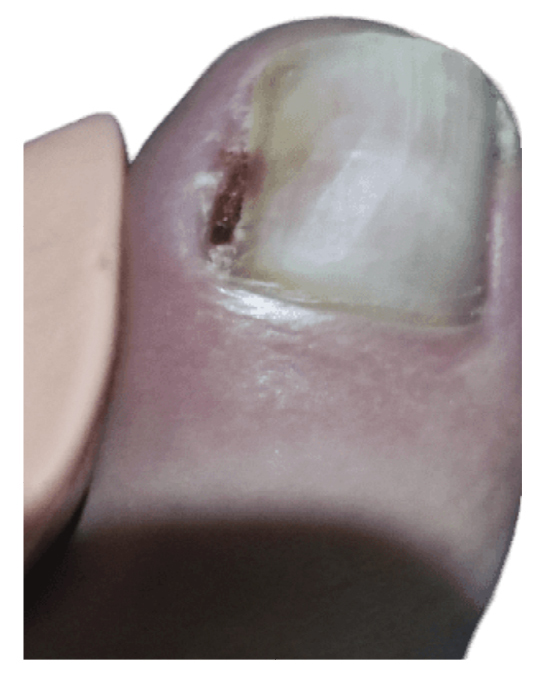

The patient initially showed improvement in pain, although it never completely subsided (Figure 4). She reported recurrence of the nail lesion, which led her to seek a second opinion 6 weeks after the intervention with another podiatrist. This latter podiatrist, on December 27th (Figure 5), performed a bacterial culture of the lesion, which turned out negative, and also evaluated the lesion by ultrasound (without report). On January 13th, the patient underwent surgery using the phenol-alcohol technique on the lateral border of the first toe of the left foot (Figure 6).

Figure 5. 16th week. Negative microbiological culture and sonograhpic assessment (not available).

Figure 6. 18th week. Second intervention by means of phenol-alcohol partial matricectomy.